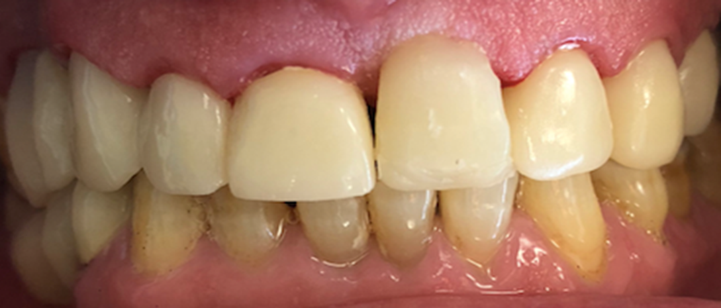

Resident Case Photos

The following are before and after photos of dental patients who have been treated by the residents at NYC Health + Hospitals/South Brooklyn Health. To apply to the program visit the Dental GPR Page and click on Application Information.

Full Crowns